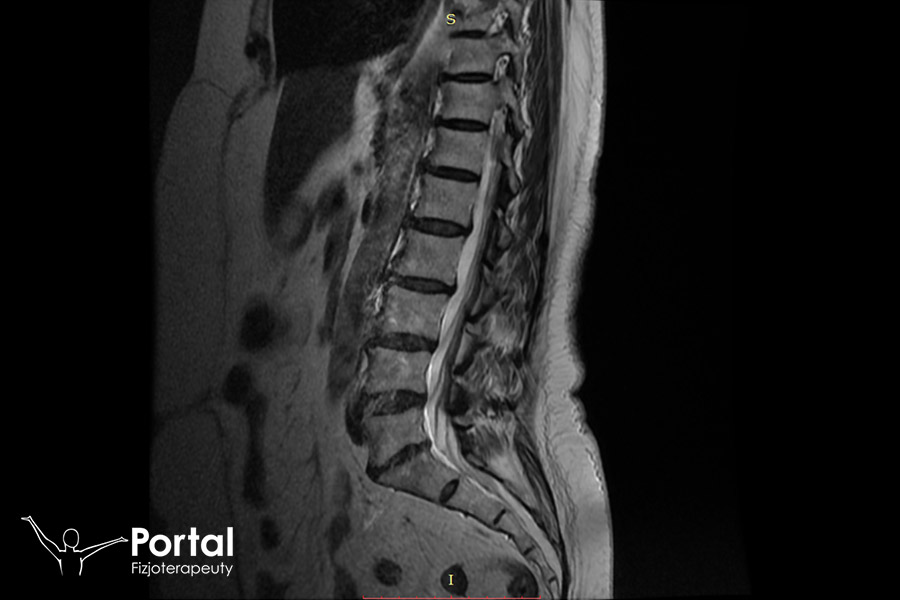

Niestabilność kręgosłupa to jedna z przyczyn dolegliwości bólowych grzbietu i wielu innych problemów zdrowotnych, np. rwy kulszowej. Choć do niedawna